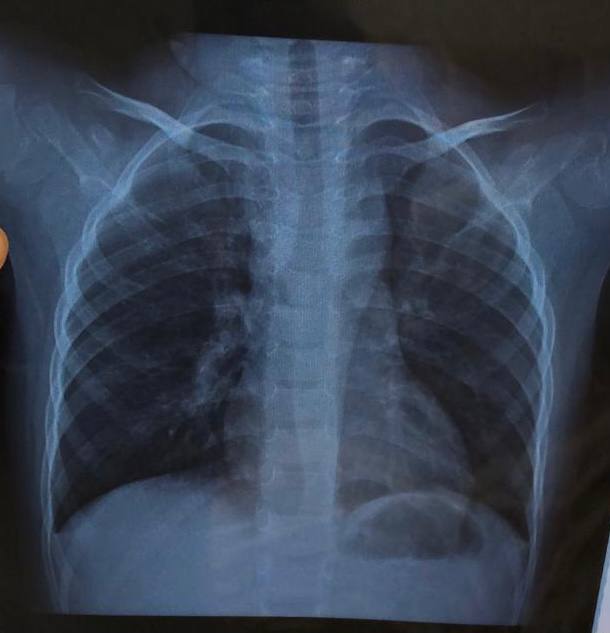

DK

4 года, кашель и темп. Пневмония в прикорневой зоне справа?